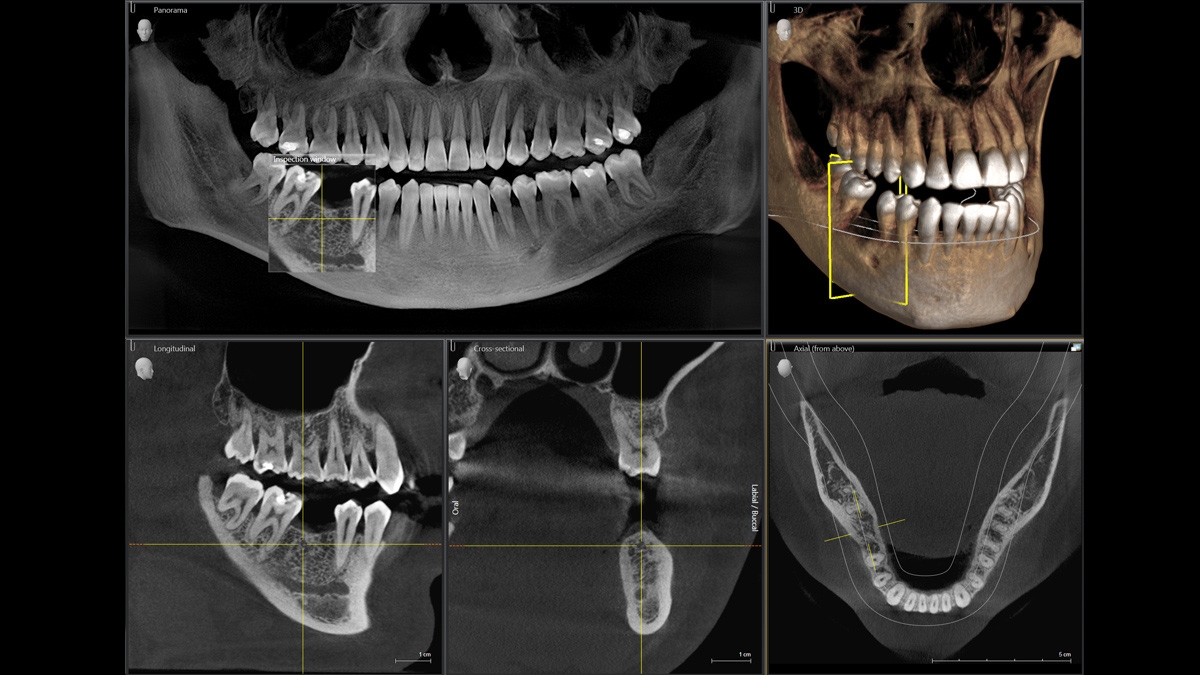

Модернизированный сенсорный экран Easypad с понятным и удобным интерфейсом позволяет выставить наилучшие параметры контрастности и разрешения. Систематизация данных по диагностике становится значительно удобнее и проще с ПО обработки изображений SIDEXIS 4, ORTHOPHOS.

1. Двух-и трёхмерные снимки совмещаются в одной программе

2. В одном окне можно сравнивать разные 3D-результаты

3. Считанные минуты уходят на просмотр анамнеза пациента.

Временная шкала Timeline – это мгновенное получение информации полного спектра проведённых обследований пациента в порядке хронологии. В результате – экономия рабочего времени и повышение качества работы в целом.